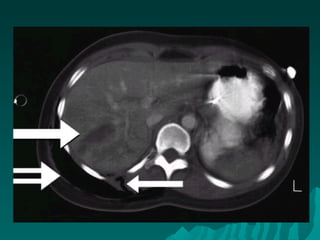

 Computed tomographyComputed tomography

 CT scan is used in the evaluation ofCT scan is used in the evaluation of

patients with stab wounds to the flank andpatients with stab wounds to the flank and

the back and in the evaluation of selectedthe back and in the evaluation of selected

patients with abdominal stab wounds andpatients with abdominal stab wounds and

GSWsGSWs